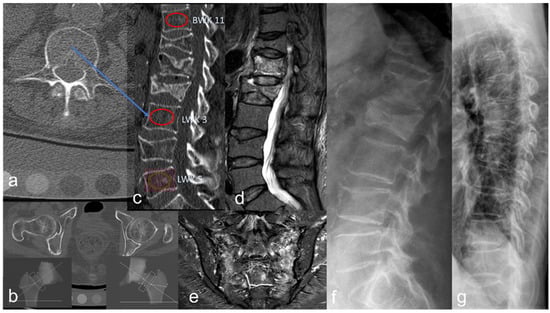

2.4. Fracture Detection